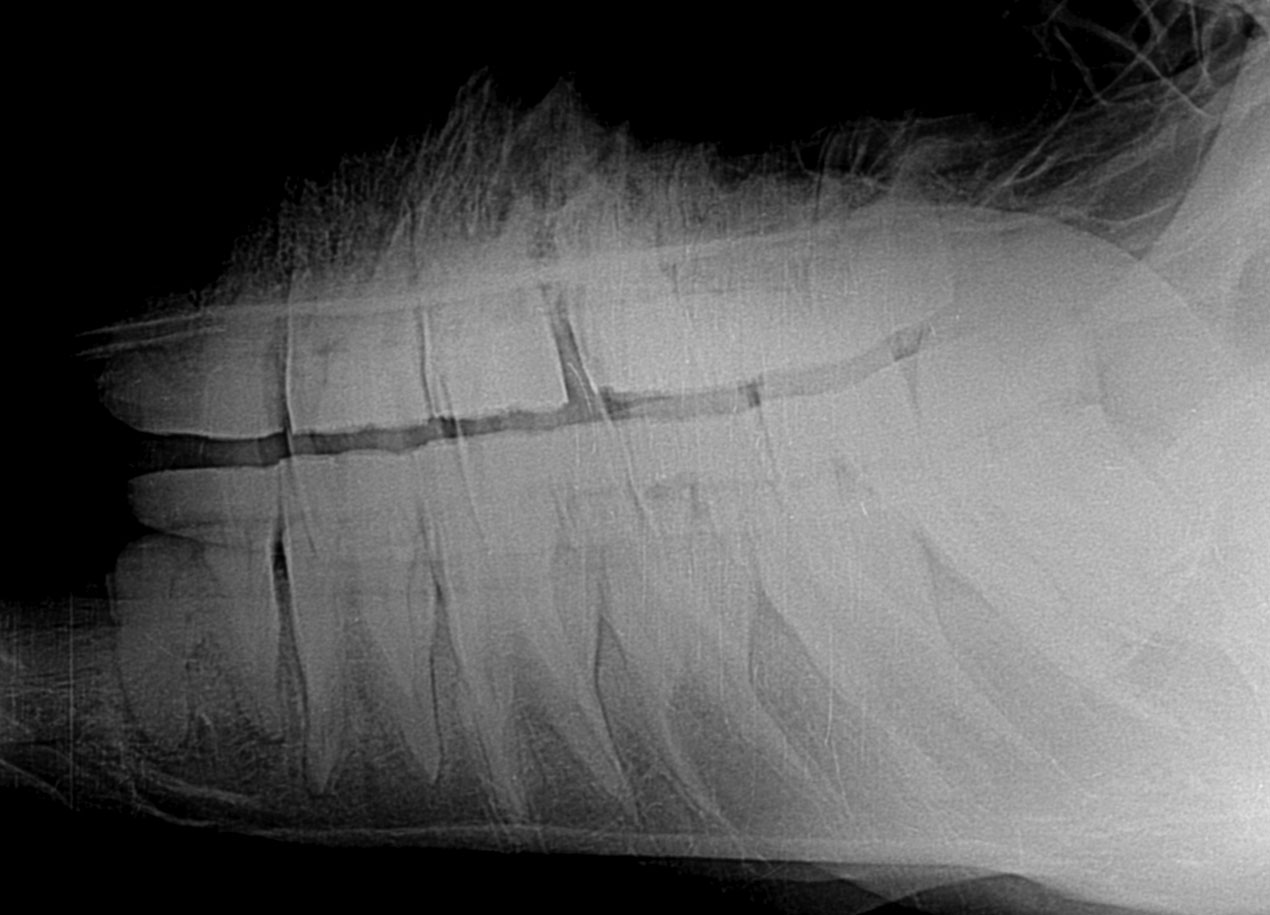

•Paradontalerkrankungen (Zahnzwischenräume erweitern sich durch Druck auf einzelne Zähne, in diese dringt Futter ein, was eine Entzündung hervorruft--> Siehe Photo und Röntgenbild)